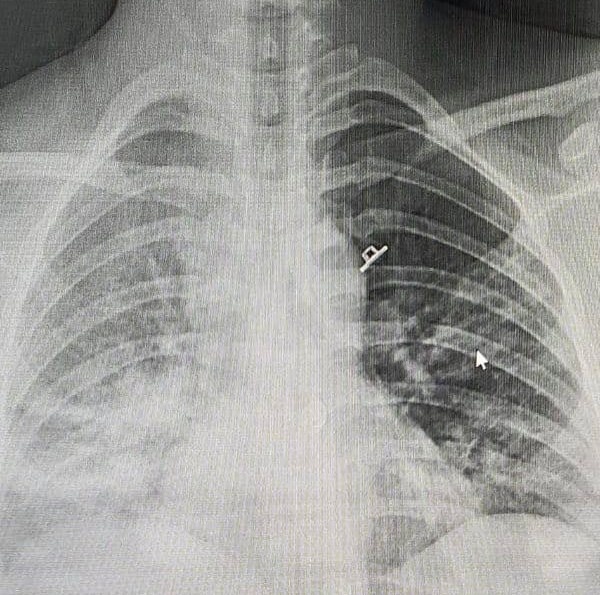

Hình ảnh XQ phổi của thai phụ. Ảnh: Bộ Y tế.

Hình ảnh phim chụp X-quang ngực của bệnh nhân có tổn thương dạng kẽ ở hai đáy phổi.